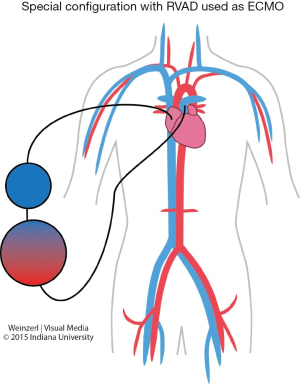

In special configuration when RVAD used as ECMO the oxygenated blood is delivered to the pulmonary artery so the blood bypass only the right heart (Figure 5).